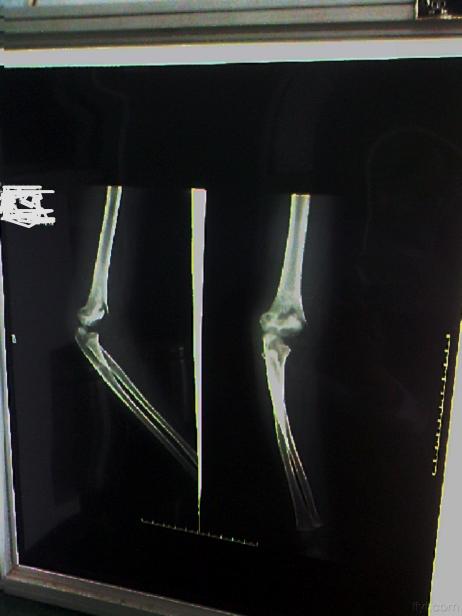

诊断方法

:医生通过体格检查结合上臂 X 光片,明确骨折部位、类型及是否合并移位、血管神经损伤;